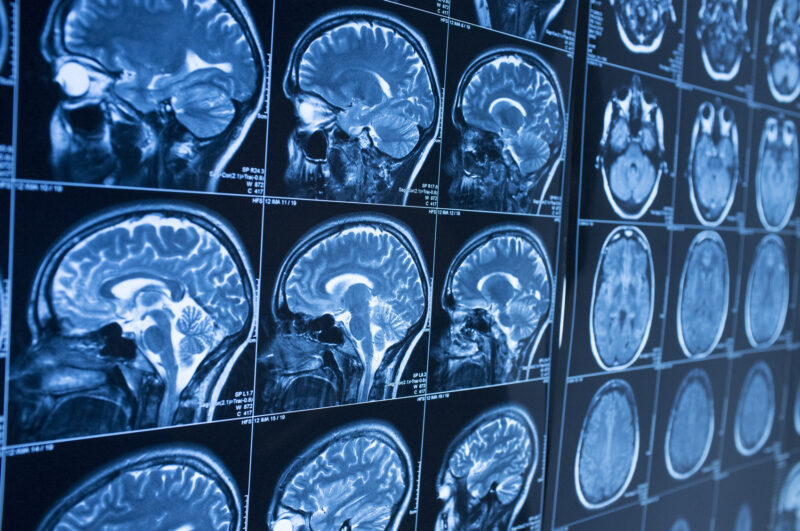

If you or a loved one has suffered a traumatic brain injury (TBI) in Charlotte, NC, you may have heard the term “Glasgow Coma Scale” (GCS) mentioned by doctors or attorneys. This scale is a critical tool used by medical professionals to assess the severity of brain injuries.

The GCS is a standardized neurological tool developed about five decades ago by doctors Bryan Jennett and Graham Teasdale at the University of Glasgow. It is used to assess a person’s level of consciousness after a brain injury

Doctors may use the scale to evaluate brain injuries after car accidents, falls, and other traumatic events.